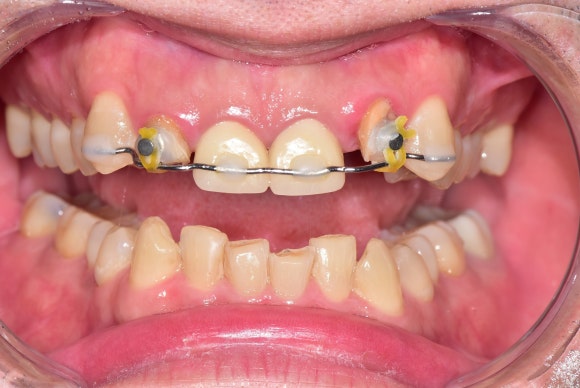

20250228

교정적정출술은 인접치아에 와이어를 붙이는 것에서 시작합니다.

꺼낼 치아에 고무줄을 연결합니다.

영차! 영차!